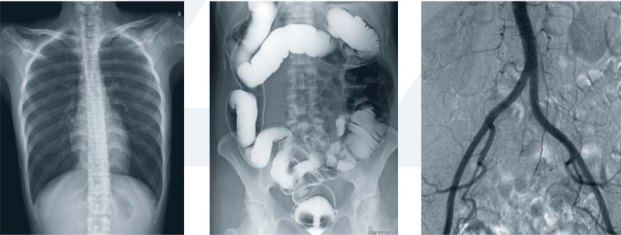

醫(yī)用dr設(shè)備是一種新的成像技術(shù),可直接將X線光子通過成像板轉(zhuǎn)換為數(shù)字化圖像,實現(xiàn)了模擬X圖像向數(shù)字化X線圖像的轉(zhuǎn)變。主要由X線球管、X線高壓發(fā)生器、數(shù)字探測器、機械部件和圖像系統(tǒng)等組成。

目前,醫(yī)用dr設(shè)備的應(yīng)用越來越普及,市場上的dr設(shè)備種類也比較多。主要以所使用的數(shù)字影像探測器類型來分類,有采用TFT(thin-film technology薄膜工藝學(xué))技術(shù)的平板探測器,其中又分為非晶硒直接轉(zhuǎn)換探測器和熒光晶體(碘化艷、硫酸釓等)—非晶硅間接轉(zhuǎn)換探測器,還有熒光晶體—光學(xué)系統(tǒng)—CCD/CMOS型DR系統(tǒng),以及各類線陣掃描型數(shù)字成像系統(tǒng)。

3.對骨結(jié)構(gòu)、關(guān)節(jié)軟骨及軟組織的顯示優(yōu)于傳統(tǒng)的X線成像,還可進行礦物鹽含量的定量分析;易于顯示縱隔結(jié)構(gòu)如血管和氣管;對結(jié)節(jié)性病變的檢出率高于傳統(tǒng)的X線成像;在觀察腸管積氣、氣腹和結(jié)石等含鈣病變優(yōu)于傳統(tǒng)X線圖像;體層成像優(yōu)于X線體層攝影;胃腸雙對比造影在顯示胃小區(qū)、微小病變和腸粘膜皺襞上,數(shù)字化圖像優(yōu)于傳統(tǒng)的X線造影。

4.醫(yī)用dr設(shè)備的成像過程是數(shù)字化成像過程。X線探測器將透過人體的X線能量轉(zhuǎn)換和數(shù)字化,包括X線采集、轉(zhuǎn)換、量化、傳輸、處理、顯示等在內(nèi)的整個X線成像過程均是數(shù)字化信息處理過程。數(shù)字化攝影模式改變了圖像信息形成的基礎(chǔ),X線信號的載體不再是屏/片系統(tǒng),而是由眾多種類的X線探測器取代,X線探測器通過不同的信號采集原理,把代表人體信息的X線強度分布,采用數(shù)字化模式進行采集、轉(zhuǎn)換、儲存、處理和顯示。